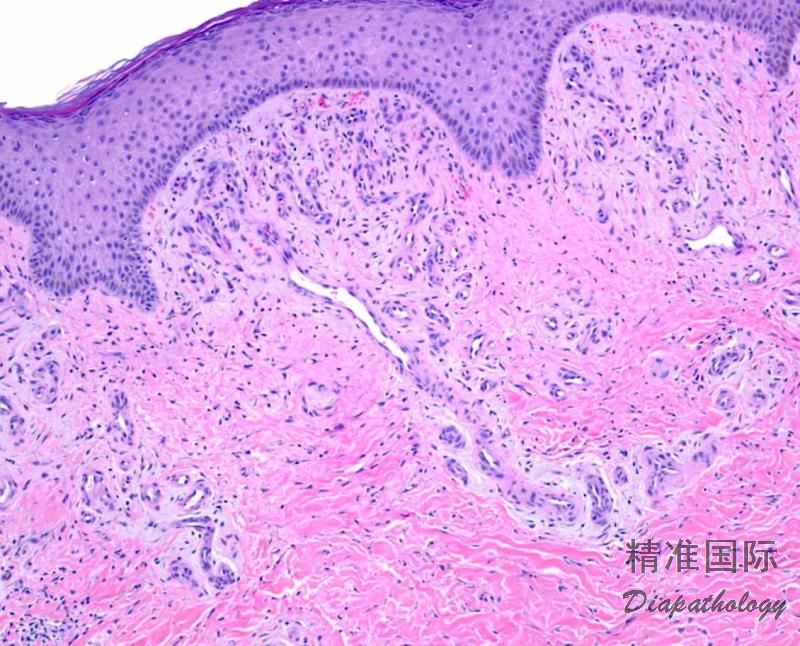

脂性硬皮病

Lipodermatosclerosis

概述:

周围血管病变引起的脂膜炎常见中年或老年肥胖的女性下肢对称的硬斑, 有萎缩及色素沉着